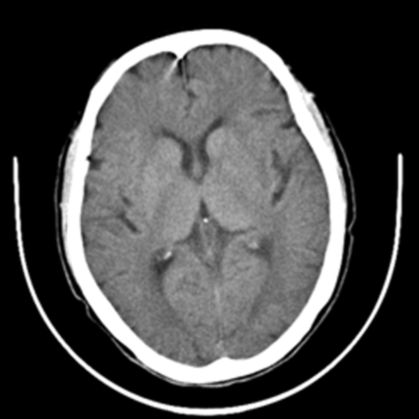

一、头颅CT

CT(Computed Tomography),即电子计算机断层扫描,它是利用精确准直的X线束,与灵敏度极高的探测器一同围绕人体的某一部位作一个接一个的断面扫描,具有扫描时间快,图像清晰等特点,是急性脑血管病最常用的首选检查方法。优点是成像速度快,价格低廉,无需预约,无扫描条件限制,只要患者安静平躺几分钟即可完成。